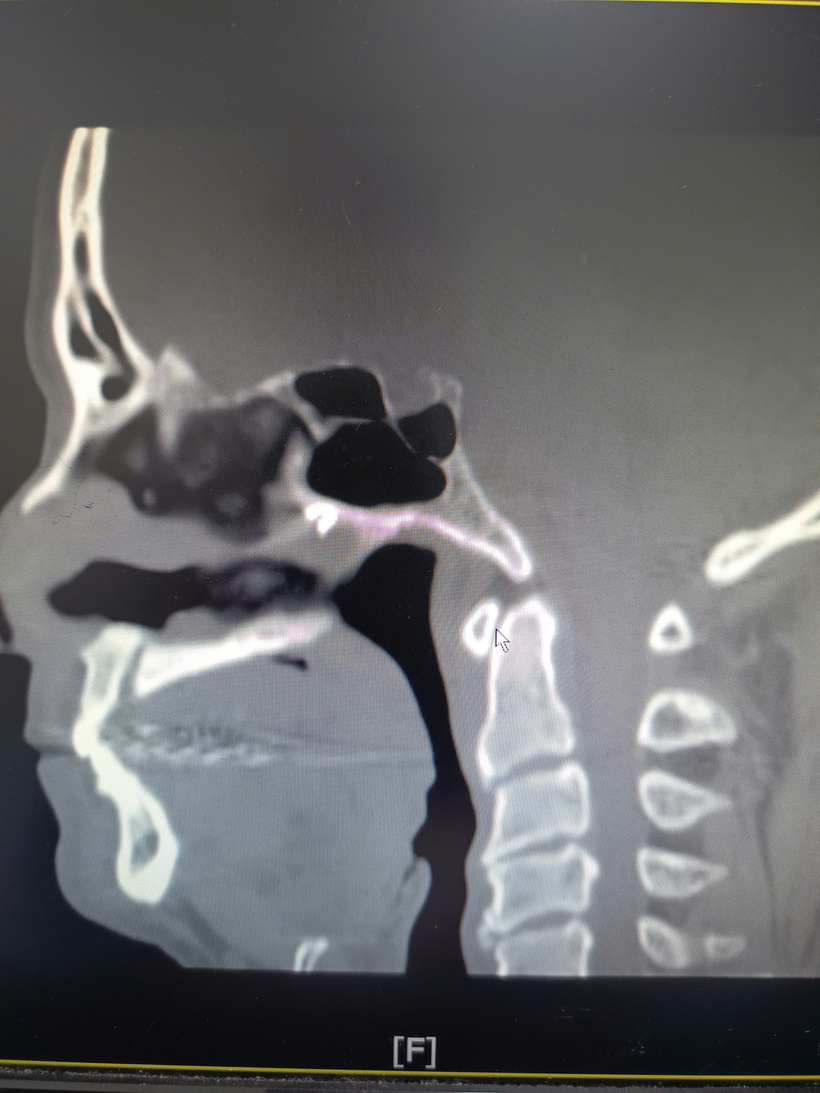

Tại lần thăm khám này, bệnh nhân được chỉ định nội soi tai mũi họng và chụp cắt lớp vi tính (CLVT) xoang. Kết quả nội soi cho thấy vách ngăn mũi bị thủng, niêm mạc biến đổi mạn tính. Đặc biệt, hình ảnh CLVT phát hiện một dị vật cản quang nằm ở phần sau, trên của vách ngăn mũi phải, cách cửa mũi trước khoảng 7 cm, sát mặt trước xoang bướm.

Theo các bác sĩ, kết quả CLVT đóng vai trò then chốt, giúp xác định chính xác vị trí dị vật, nguyên nhân gây viêm mạn tính kéo dài và các cơn đau đầu dai dẳng của bệnh nhân trong nhiều năm.

Trên cơ sở chẩn đoán xác định, ê-kíp đã xây dựng kế hoạch phẫu thuật chi tiết. Trong quá trình phẫu thuật, các bác sĩ đã lấy ra thành công dị vật tồn dư, nhiều khả năng là mảnh dụng cụ phẫu thuật bị gãy từ ca mổ năm 1984. Dị vật nằm sâu, sát vùng trước xoang bướm, vị trí khó tiếp cận, lý giải vì sao các lần phẫu thuật trước đó không phát hiện được.